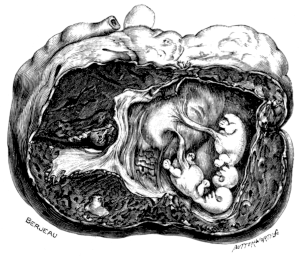

| 23. | A Gravid Uterus in Sagittal Section | 79 |

| 22. | A Uterus distorted by Fibroids | 76 |